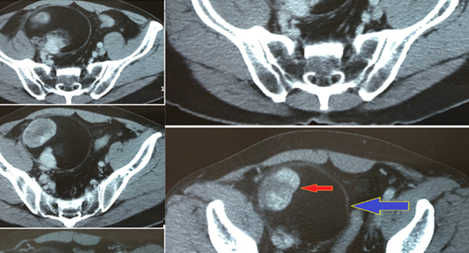

Ngày 25/2, Bệnh viện quận 9 (TPHCM) cho biết đã phẫu thuật khẩn cấp cứu sống thai phụ đang mang thai ở tháng thứ 9, bị vỡ tử cung trên vết mổ cũ vì không khám thai định kỳ.

Khoảng 10h58 sáng 12-12-2017, Bệnh viện (BV) Nhân Dân Gia Định TP Hồ Chí Minh nhận được tín hiệu báo động đỏ yêu cầu hỗ trợ 1 bệnh nhân bị chảy máu trong mổ không kiểm soát được tại BV quận . Ngay lập tức ê-kíp trực gồm các bác sĩ chuyên khoa lồng ngực mạch máu, khoa Ngoại tổng quát cùng nhân viên xét nghiệm đã nhanh chóng vào cuộc.